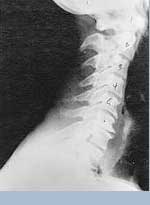

Phase Three Subluxation Degeneration is caused by subluxations that have been continuing on for between 40 and 65 years. This phase has all of the attributes of the previous phases, only worse. The curvatures are abnormal, the disc spaces are vastly decreased and changed. Calcium changes on the spine are abundant in this phase. Normally, people in phase three have a restricted range of motion and probably exhibit symptoms of some kind. In phase three the vertebrae show obvious changes and mutations in shape. Projections made of calcium, sometimes referred to as "spurs or lipping", can be readily seen on x-ray. Chiropractic reconstructive care for patients in phase three ranges from 2.5 years to 3.5 years. This does not mean that at the end of this time that any or all of the calcium changes will be gone. In many instances the body adapts to the presence of the calcium and positive changes can only be measured from a functional standpoint. As before, if Phase Three Subluxation Degeneration is left unchecked it slowly advances onward into the next phase.